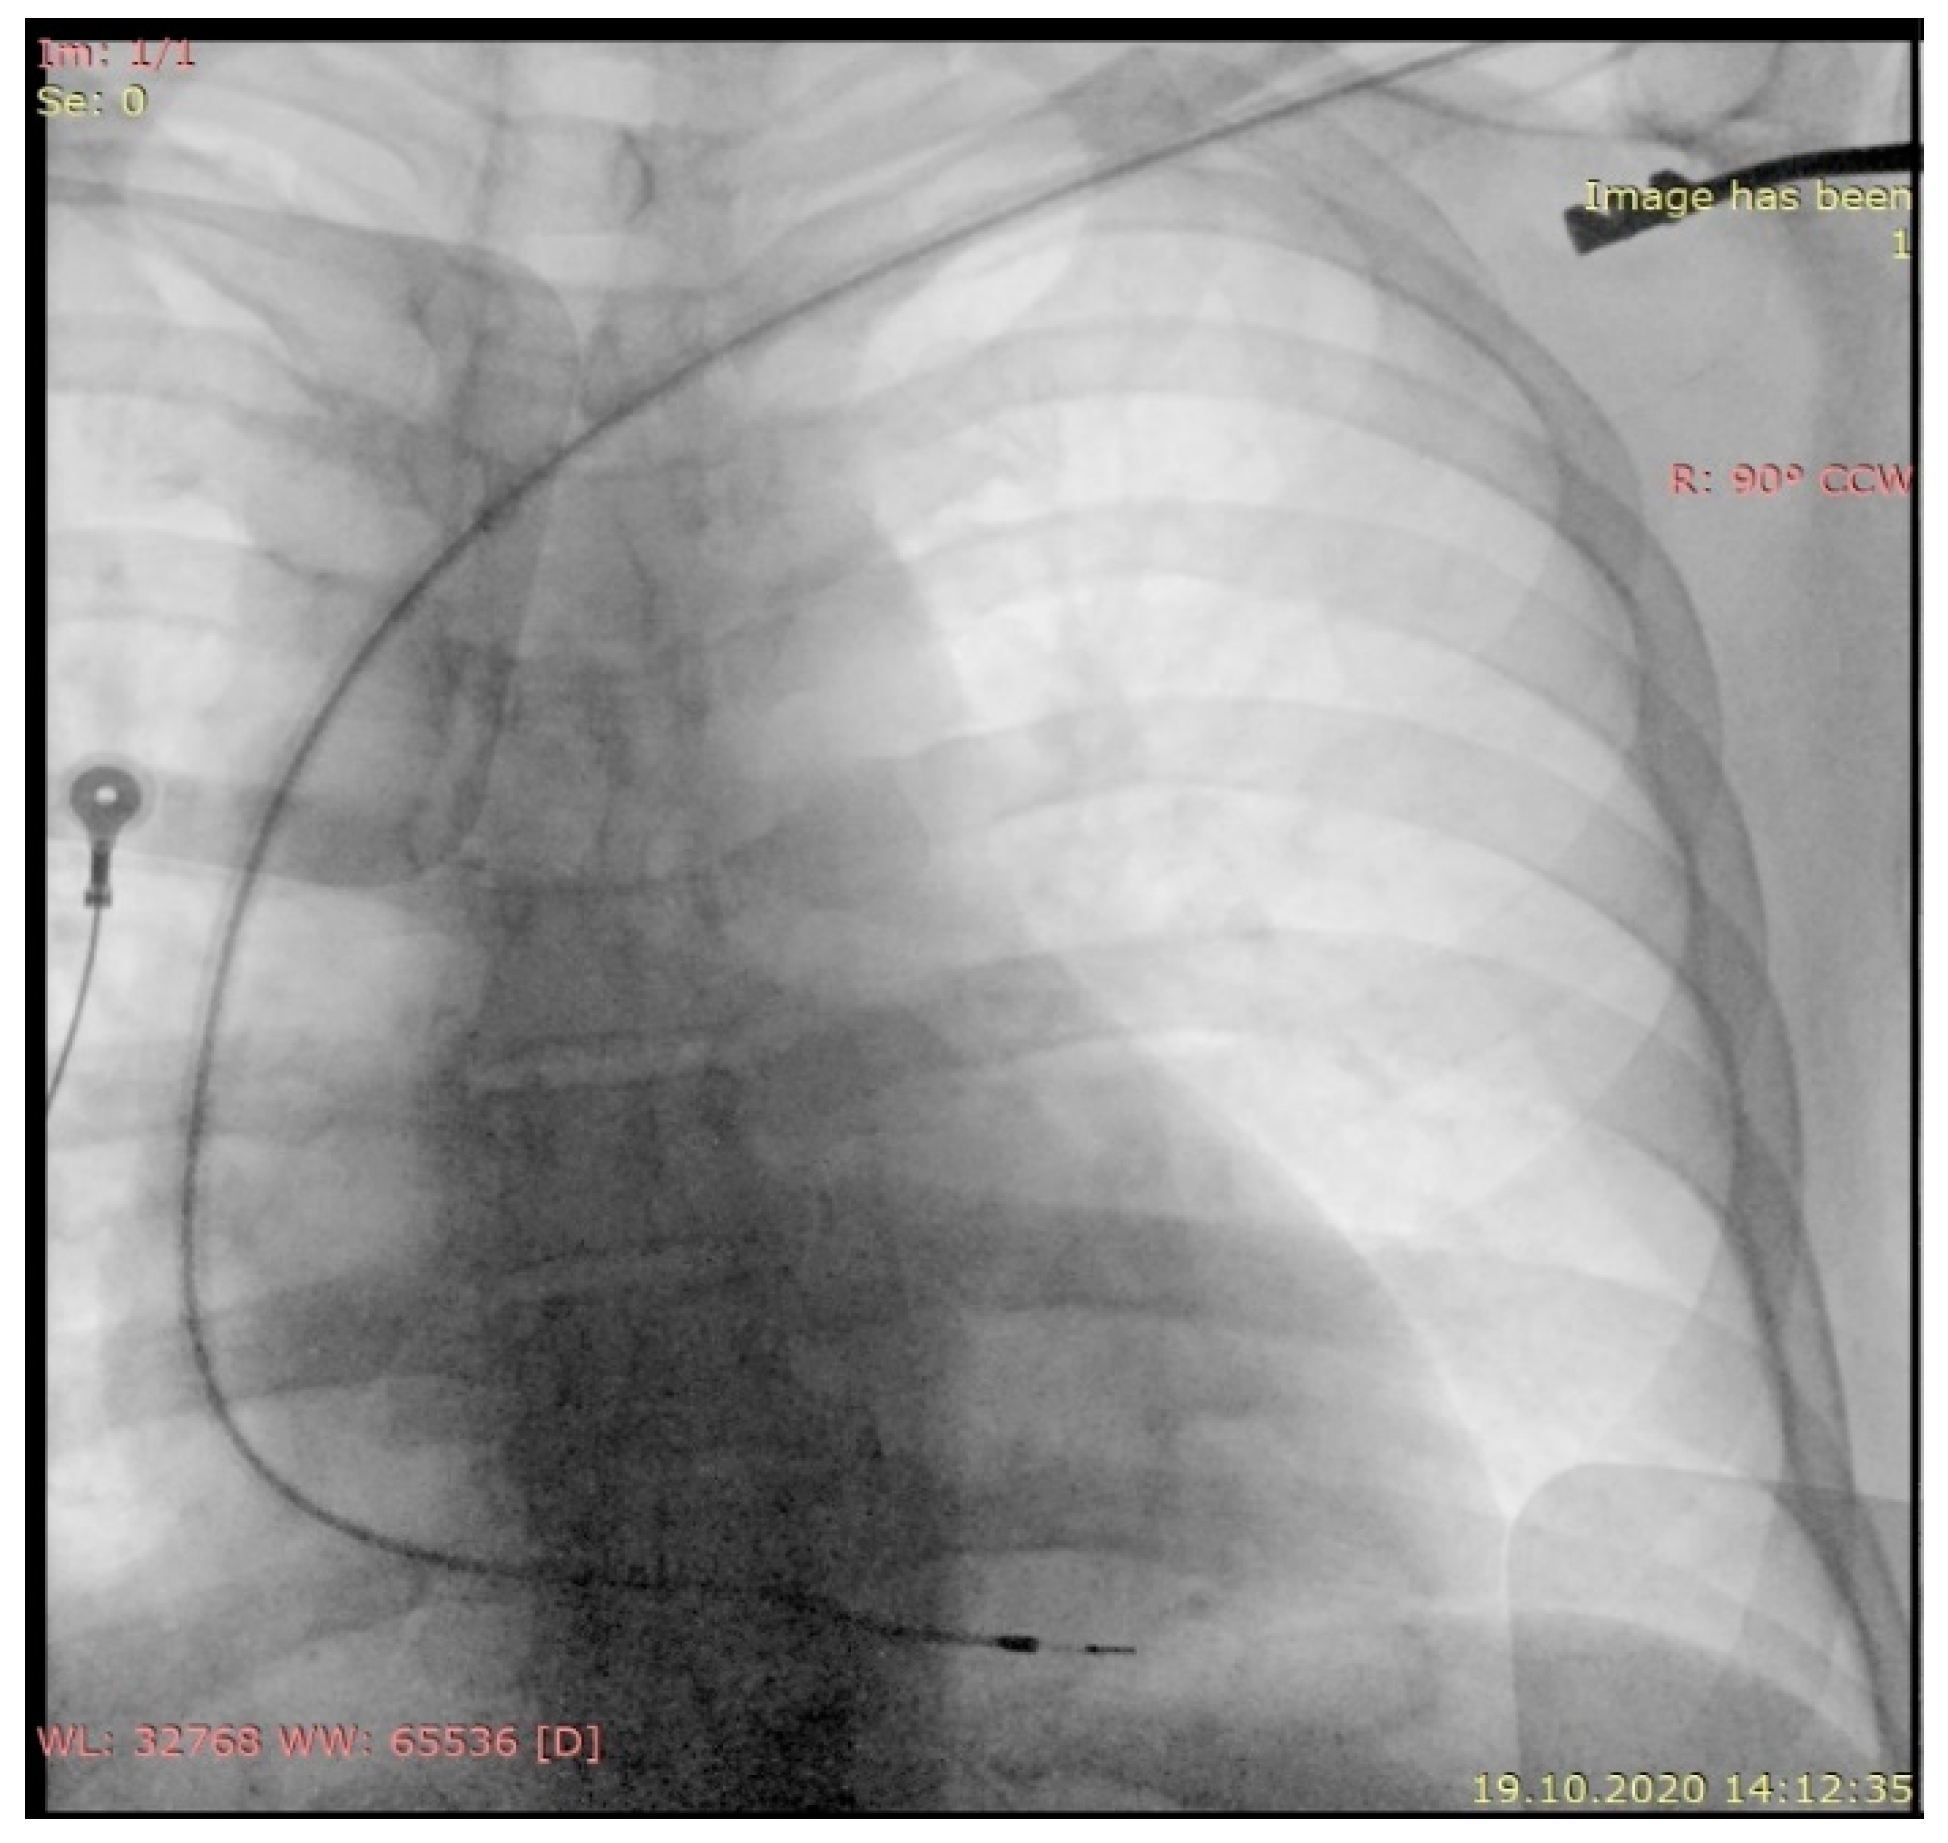

2. Case Report